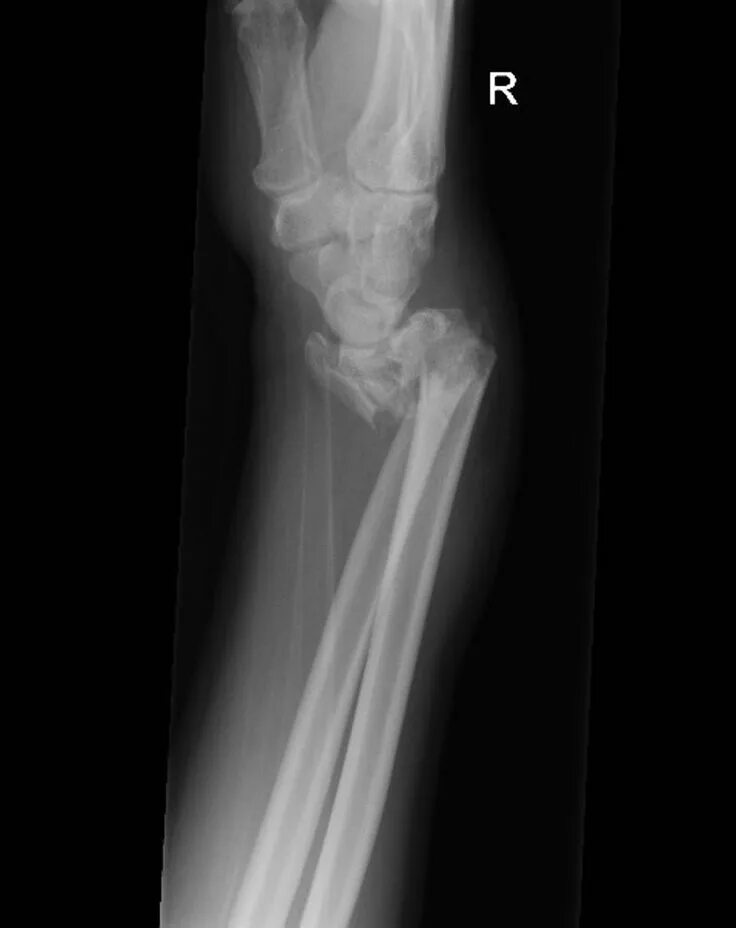

Перелом смита